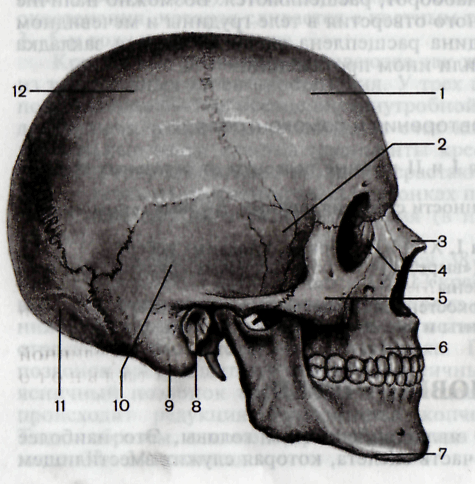

Анатомия детского черепа: Рентгеновские снимки и описание